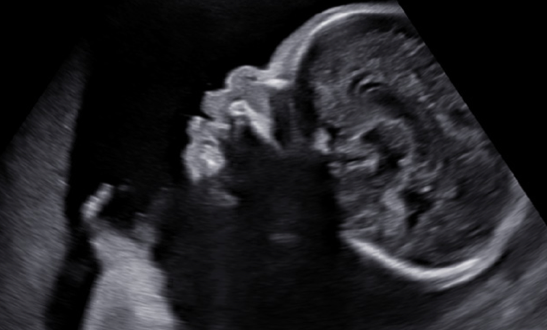

Fig 2. Bosa frontala